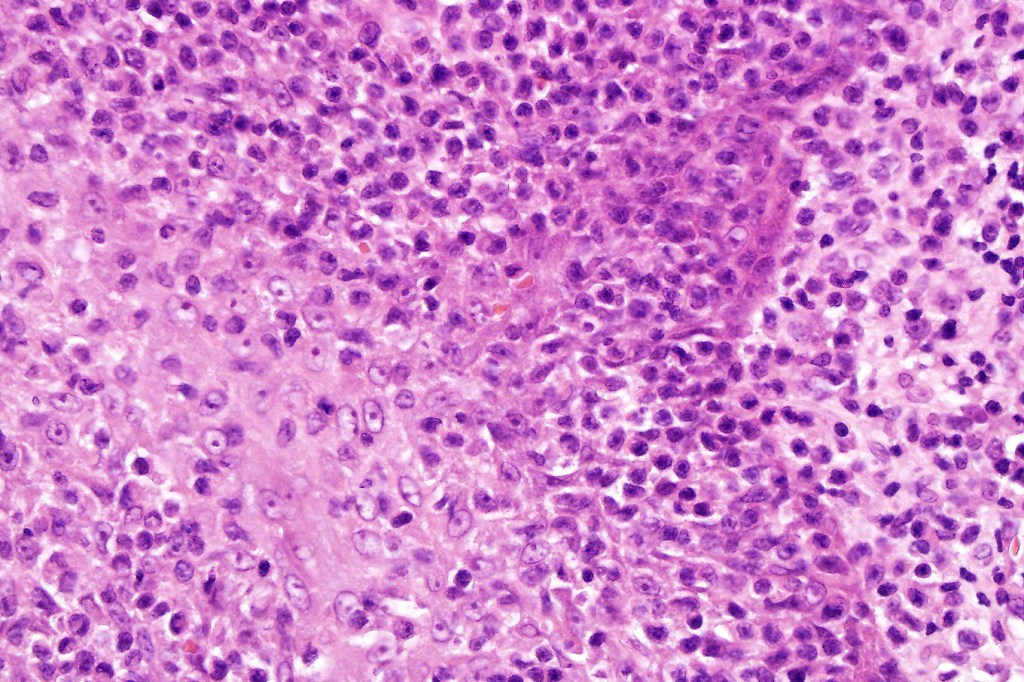

Histological features

•Follicular infiltration by atypical lymphocytes & Sézary cells

•Eosinophils sometimes conspicuous (eosinophilic folliculitis-like appearance)

•Large cell transformation occasionally present